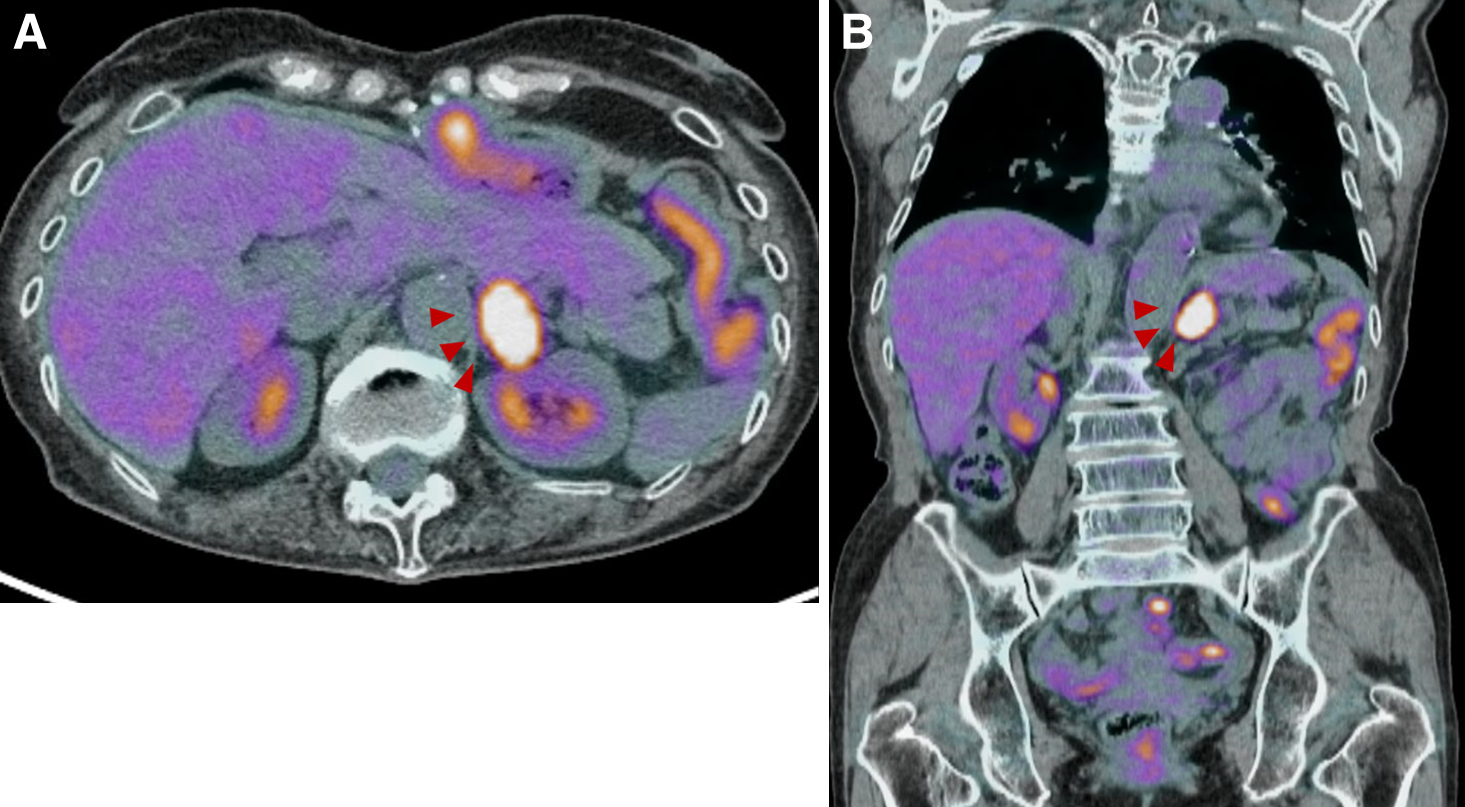

腹部・骨盤部PET-CT所見:左副腎への強いFDG集積を認めた(Fig. 2A, B,矢頭).縦隔を含め,ほかに明らかな集積は認めなかった.

PET/CT showed high accumulation of FDG in the left adrenal region (A: axial, B: sagittal, red arrowheads). There were no other obvious accumulations, including the mediastinum.